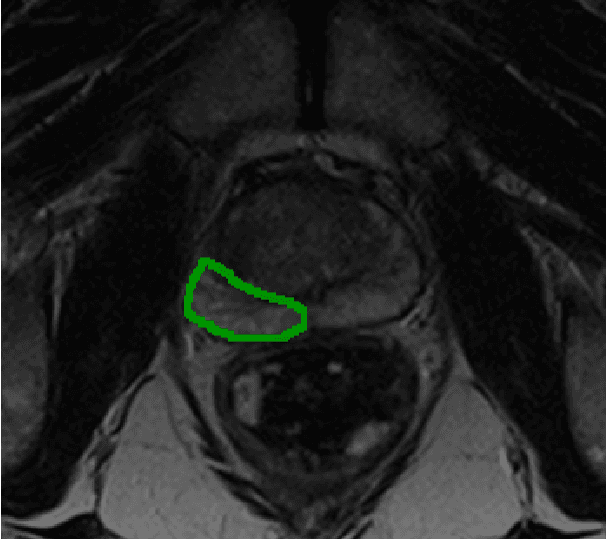

Project award

The team is using deep learning methods to connect prostate cancer imaging with past tissue evidence, enabling personalised targets to be forecasted without requiring a biopsy.

Project leads: Yipeng Hu, Geoffrey Sonn

Collaborating institutions: UCL, Canary Center at Stanford (prior partner)